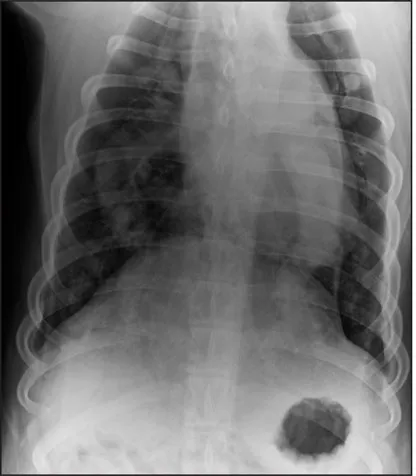

CASE 1.1 A 7-year-old neutered male Labrador Retriever who was hit by a car. You obtain these thoracic radiographs: Figs. 1.1a, b, left and right lateral projections, respectively; Figs. 1.1c, d, ventrodorsal and dorsoventral projections, respectively.

1.1d